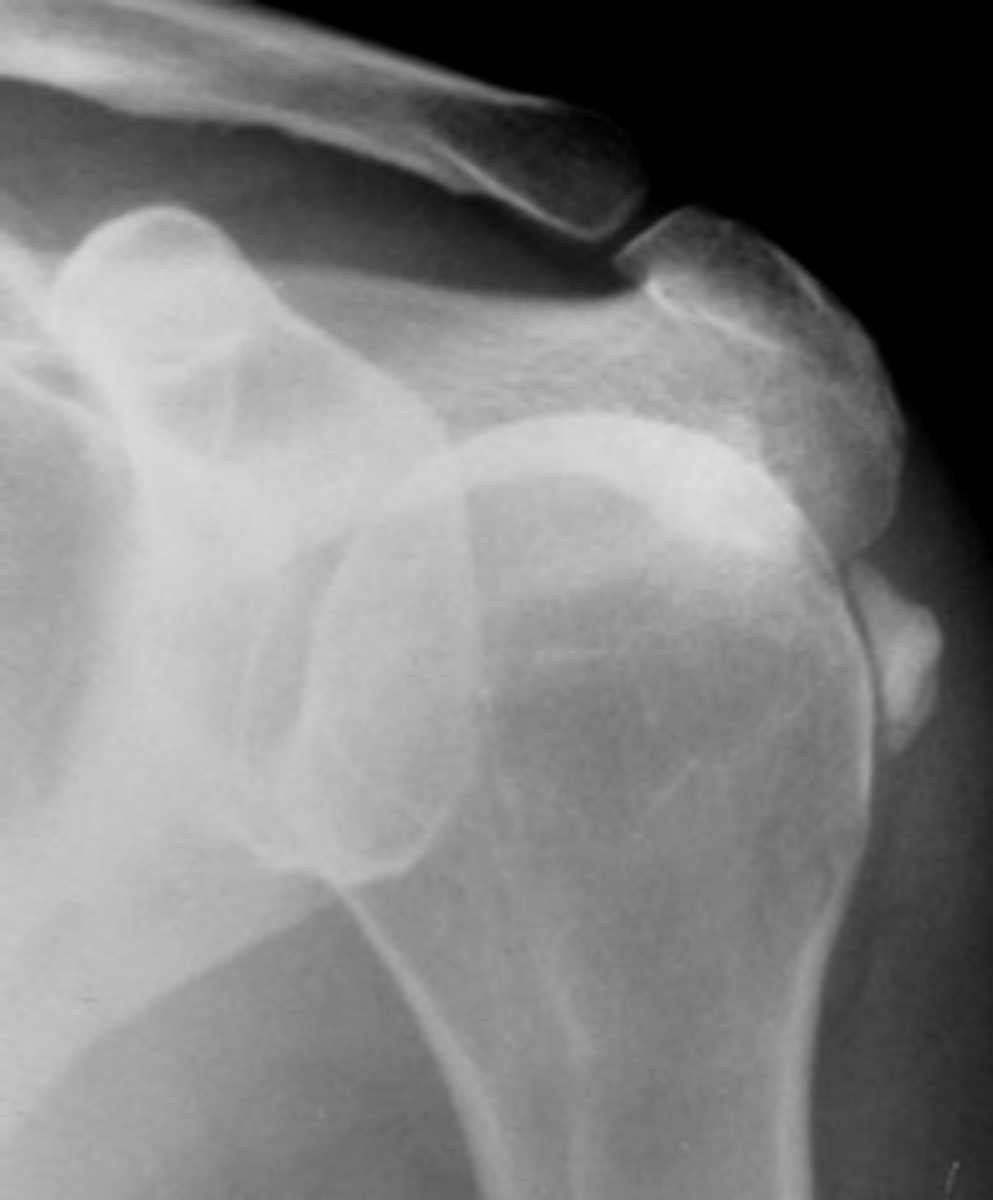

- Soft tissue swelling

- Chondrocalcinosis

- Severe degeneration

- Pyrophosphate arthropathy

- Articular destruction

State the radiographic findings of calcium pyrophosphate dihydrate crystal deposition disease (CCPD)